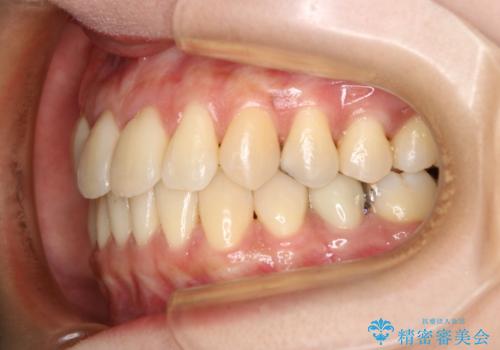

前歯が内側に入っている:インビザライン治療

- 上の前歯は内側に入っていることが気になりご相談にいらした方です。インビザラインにて治療を行いました。

1週間でのマウスピース交換を指示していましたが、20時間以上使えない時があると不安との事で、2週間ごとの交換にしていました(実際はほとんど20時間以上使用できていたようです)。治療終了まで時間はかかりましたが、最終的に綺麗に並べることができ、大変喜んでいただけました。